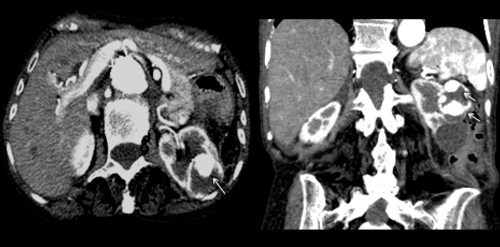

La Categoría III muestra engrosamientos lisos o irregulares de la pared o de los septos intra quísticos y existencia de realce medible en TC y RMI. Se consideran masas indeterminadas y precisan de primera instancia cirugía, nefrectomía parcial o ablación por radiofrecuencia, salvo contraindicaciones clínicas.(19, 21) Aproximadamente el 40%-60% son lesiones malignas (carcinomas renal quístico), siendo el restante benignas, que incluyen quistes hemorrágicos, infectados crónicos o calcificaciones parietales, nefrona quístico multiloculado, quistes multilobulados, quistes con tabiques complejos, etc. (Anexos 9 y 10).

La Categoría IV presenta captación de un componente sólido intra quístico, muestra realces nodulares fuera de la pared y de los septos interpuestos en el área quística compleja, calcificaciones gruesas, vascularizadas con un importante realce con contraste yodado IV. En realidad, son lesiones malignas con componente quístico. Se trata de neoplasias quísticas, y precisan cirugía y estadificación.(19, 21) (Anexos 11 y 12).